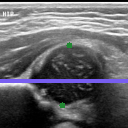

The correlation statistics are already high enough for our automated tool to be widely adopted for infant hip screening. It is nevertheless essential to acknowledge that the false negative cases are not to be taken lightly. In Fig. 5 we illustrate the subtle differences between individual scans from the four possible categories. Fig. 5(a) shows a true positive example, with AFHC=39.6%, an error of less than 0.04% to SGT. It is worth noting that, for 128×128128128128{\times}128 pixel images, a disagreement of one pixel represents a percentage difference of 0.78% across the whole image, and approximately 1.5% across the span of the femoral head structure. Fig. 5(b) shows a true negative example, with AFHC=62.4%, an error of less than 0.39% to SGT. Fig. 5(c) shows the most severe of the false positives. The algorithm under-segments the lowermost component of the femoral head, with AFHC=43.3%, compared to a SGT FHC of 50.4%. Fig. 5(d) shows the most severe of the false negatives. The algorithm over segments the lowermost component of the femoral head and also slightly over segments the ilium on its upper edge by including a small bump of cartilage. There is only little of the horizontal length of the ilium visible in the image; this affects the ilium edge disproportionately, and thus the algorithm calculates AFHC=60.1%, whereas the SGT FHC is 49.9% (a figure which would have caused a clinician to keep the patient under observation).

Refer to caption

(b)

Fig. 5: Qualitative analysis of AFHC% and its corresponding diagnostic outcomes: (a) True positive. (b) True negative. (c) False positive. (d) False negative diagnosis.